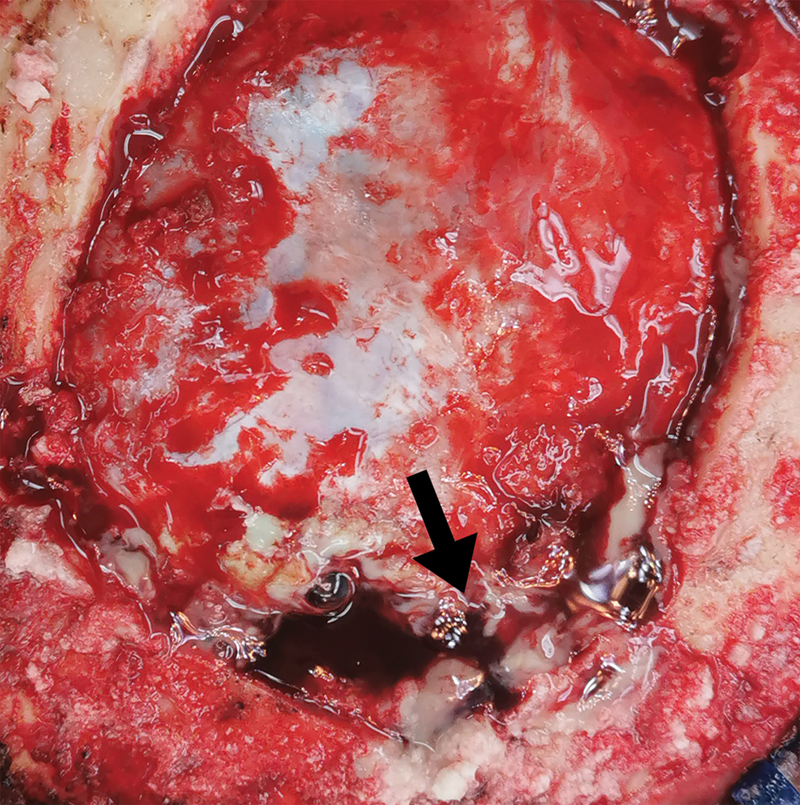

脑曲霉菌病是一种机会性真菌感染,在免疫功能正常的患者中极为罕见。这些感染的主要病因通常涉及鼻腔和血液传播。一名 62 岁的男性患者注重养生,出现间歇性、非进行性枕部头痛、全身阵挛强直发作和意识改变。计算机断层扫描显示,两侧枕叶有多个边缘强化的小病灶,两侧枕叶邻近蝶窦和后上矢状窦汇合处有血管源性水肿。在这个病例中,发现了继发于脑曲霉菌病的上矢状窦血栓形成,这种情况以前从未在这个特定部位确诊过,但可以通过手术干预加以控制。手术切除和抗真菌治疗相结合,取得了良好的疗效。患者的预后很大程度上取决于早期诊断和及时、积极的治疗。

Cerebral aspergillosis is an opportunistic fungal infection that is exceedingly rare in immunocompetent patients. The primary etiological locations for these infections typically involve the nasal cavity and hematological dissemination. A 62-year-old male, focused on wellness, presented with intermittent, nonprogressive headaches in the occipital region, generalized clonic-tonic seizures, and altered consciousness. A computed tomography scan revealed multiple small rim-enhancing lesions in both occipital lobes, with vasogenic edema in both occipital lobes adjacent to the confluence of the sinuses and the posterior superior sagittal sinus. In this case, superior sagittal sinus thrombosis secondary to cerebral aspergillosis was discovered, a condition not previously diagnosed in this specific location but manageable through surgical intervention. A combination of surgical resection and antifungal therapy resulted in favorable outcomes. The prognosis for patients depends significantly on early diagnosis and prompt, aggressive treatment.